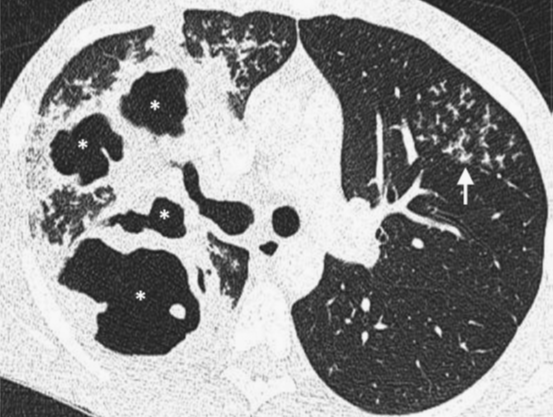

结核

1. 空洞在原发性肺结核中占40%~45%,洞壁可以薄而光滑,也可以厚而呈结节状。典型的多发空洞位于上叶尖后段。被排出的干酪样坏死物质可引起支气管播散和支气管肺炎,表现为弥漫分布的2~4 mm大小的小叶中心结节或“树芽征”和实变(图4)。

2. 约21%的空洞内有气液平面,提示细菌或真菌二重感染。在MDCT中,活动性病变通常表现为境界不清的结节、实变和小叶间隔增厚,而纤维化、瘢痕旁肺气肿、钙化结节和支气管扩张则提示慢性感染。

图4 咳嗽、咳痰,发热盗汗,体重减轻6周。右肺上叶见空洞融合(*),左肺上叶见多发“树芽征”(箭头)。痰涂片示结核分枝杆菌感染。